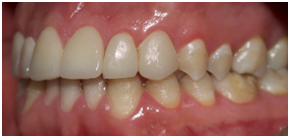

Two months later, periodontal healing was thoroughly achieved, gingival margins were stabilized and gum exposure during smile improved (Figure 3).

Figure 3 Intra oral images showing tooth size discrepancies.